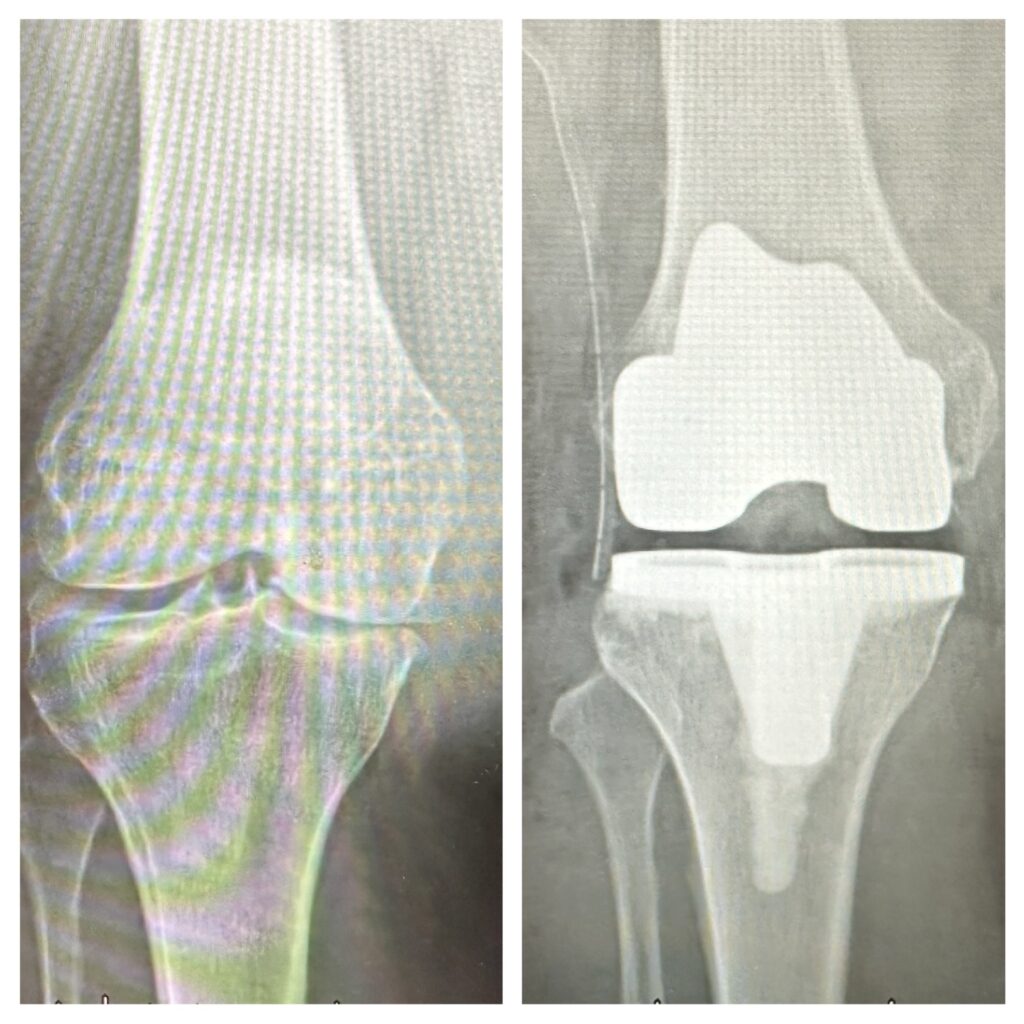

豐原醫院骨科主任呂文憲導入ERAS照護模式,成功完成膝關節「人工關節置換手術」,梁奶奶術後恢復穩定。(記者孫義方攝)

梁奶奶順利完成膝關節「人工關節置換手術」,術後疼痛明顯改善,短時間內即可重新站立並開始行走。(記者孫義方攝)